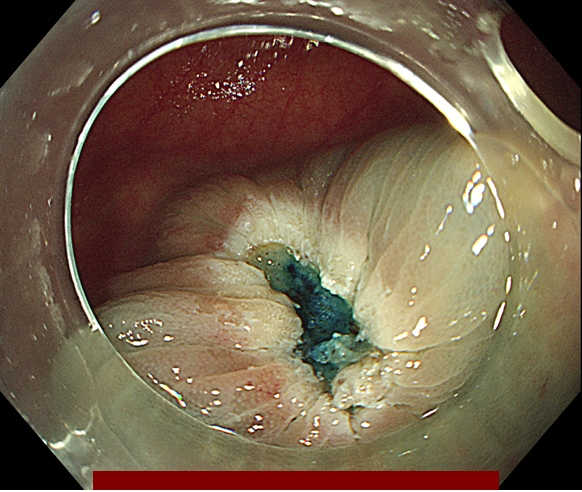

조직 검사 단독으로는 악성 세포의 존재를 배제하거나 악성 세포가 있다는 것을 확증하는데 부적절합니다. 다음 그림과 같이 악성세포가 용종에 존재하지만 조직검사로는 정상 조직을 얻을 수 있기 때문에 용종절제술로 일괄 절제해야 합니다.

오로지 용종을 완전 절제해야만 정확한 조직학적 진단이 가능합니다.

다음은 대장내시경 중 발견된 용종을 일괄 절제한 과정입니다.